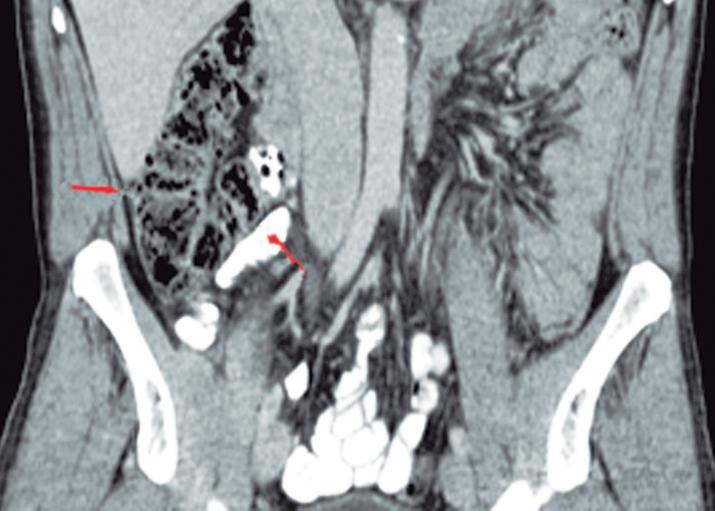

Páncreas Anular

Consiste en una anomalía de la migración del brote pancreático ventral, el cual no rota o lo hace de manera incompleta, resultando en la presencia de tejido glandular pancreático a la derecha del duodeno, rodeando a su 2° porción (Figura 8). Han sido descriptos dos subtipos: el extramural, donde el conducto de Wirsung rodea al duodeno uniéndose al conducto pancreático principal; y el intramural, donde el tejido pancreático se entremezcla con la pared duodenal y sus secreciones drenan directamente a la luz a través de conductos muy pequeños.16

En las imágenes encontramos parénquima pancreático rodeando a la 2° porción duodenal, habitualmente en toda su circunferencia y en ocasiones de manera incompleta. En la colangio-RM es posible visualizar al conducto pancreático a la derecha del duodeno, con un recorrido que se dirige a la ubicación de la papila mayor (Figura 9).17

A) Resonancia magnética secuencia T1 con gadolinio, plano axial. Las flechas señalan el parénquima del páncreas prolongado hacia la derecha “abrazando” a la 2° porción duodenal (cabeza de flecha). B) Resonancia magnética, secuencia T1 con gadolinio, plano axial, corte más caudal al previo. Las flechas nos muestran al páncreas rodeando de manera completa a la 2° porción del duodeno. C) Resonancia magnética, secuencia T2, plano coronal. La flecha señala presencia de parénquima glandular y conducto pancreático a la derecha del duodeno (cabezas de flecha). D) Resonancia magnética, secuencia T2, plano coronal, corte posterior al previo. El páncreas anular y su conducto de drenaje rodean en forma completa al duodeno (cabezas de flecha). E) Colangio-RM. El conducto del páncreas ventral (flechas) hace un giro, rodea al duodeno (cabeza de flecha) y se une al conducto pancreático principal para drenar en la papila mayor. F) Colangio-RM. La imagen magnificada muestra con mayor detalle el recorrido del conducto de Wirsung en el contexto de un páncreas anular.

El páncreas anular en neonatos, cuando es sintomático, provoca síndrome de obstrucción gástrica, clínicamente manifestado con vómitos como consecuencia de la compresión y estenosis de la 2° porción duodenal. En los adultos también puede originar obstrucción gastrointestinal, y los pacientes presentan dolor abdominal, habitualmente postprandial y/o vómitos. En menor medida puede predisponer a PAR o bien a

Más allá del diagnóstico de esta anomalía debemos buscar signos imagenológicos indirectos de obstrucción gastrointestinal, como son la dilatación gástrica y de la 1° porción duodenal (Figura 10), con estrechez de la luz del duodeno en el sitio por donde transcurre a través del páncreas anular.18,19

A) Tomografía computada con contraste, plano coronal. El páncreas anular (flecha) provoca dilatación de la 1° porción del duodeno (cabezas de flecha). B) Tomografía computada con contraste, plano axial. Flechas: páncreas anular. Cabeza de flecha: duodeno. C) Tomografía computada con contraste, plano axial, corte más caudal que el previo. Flechas: páncreas anular.